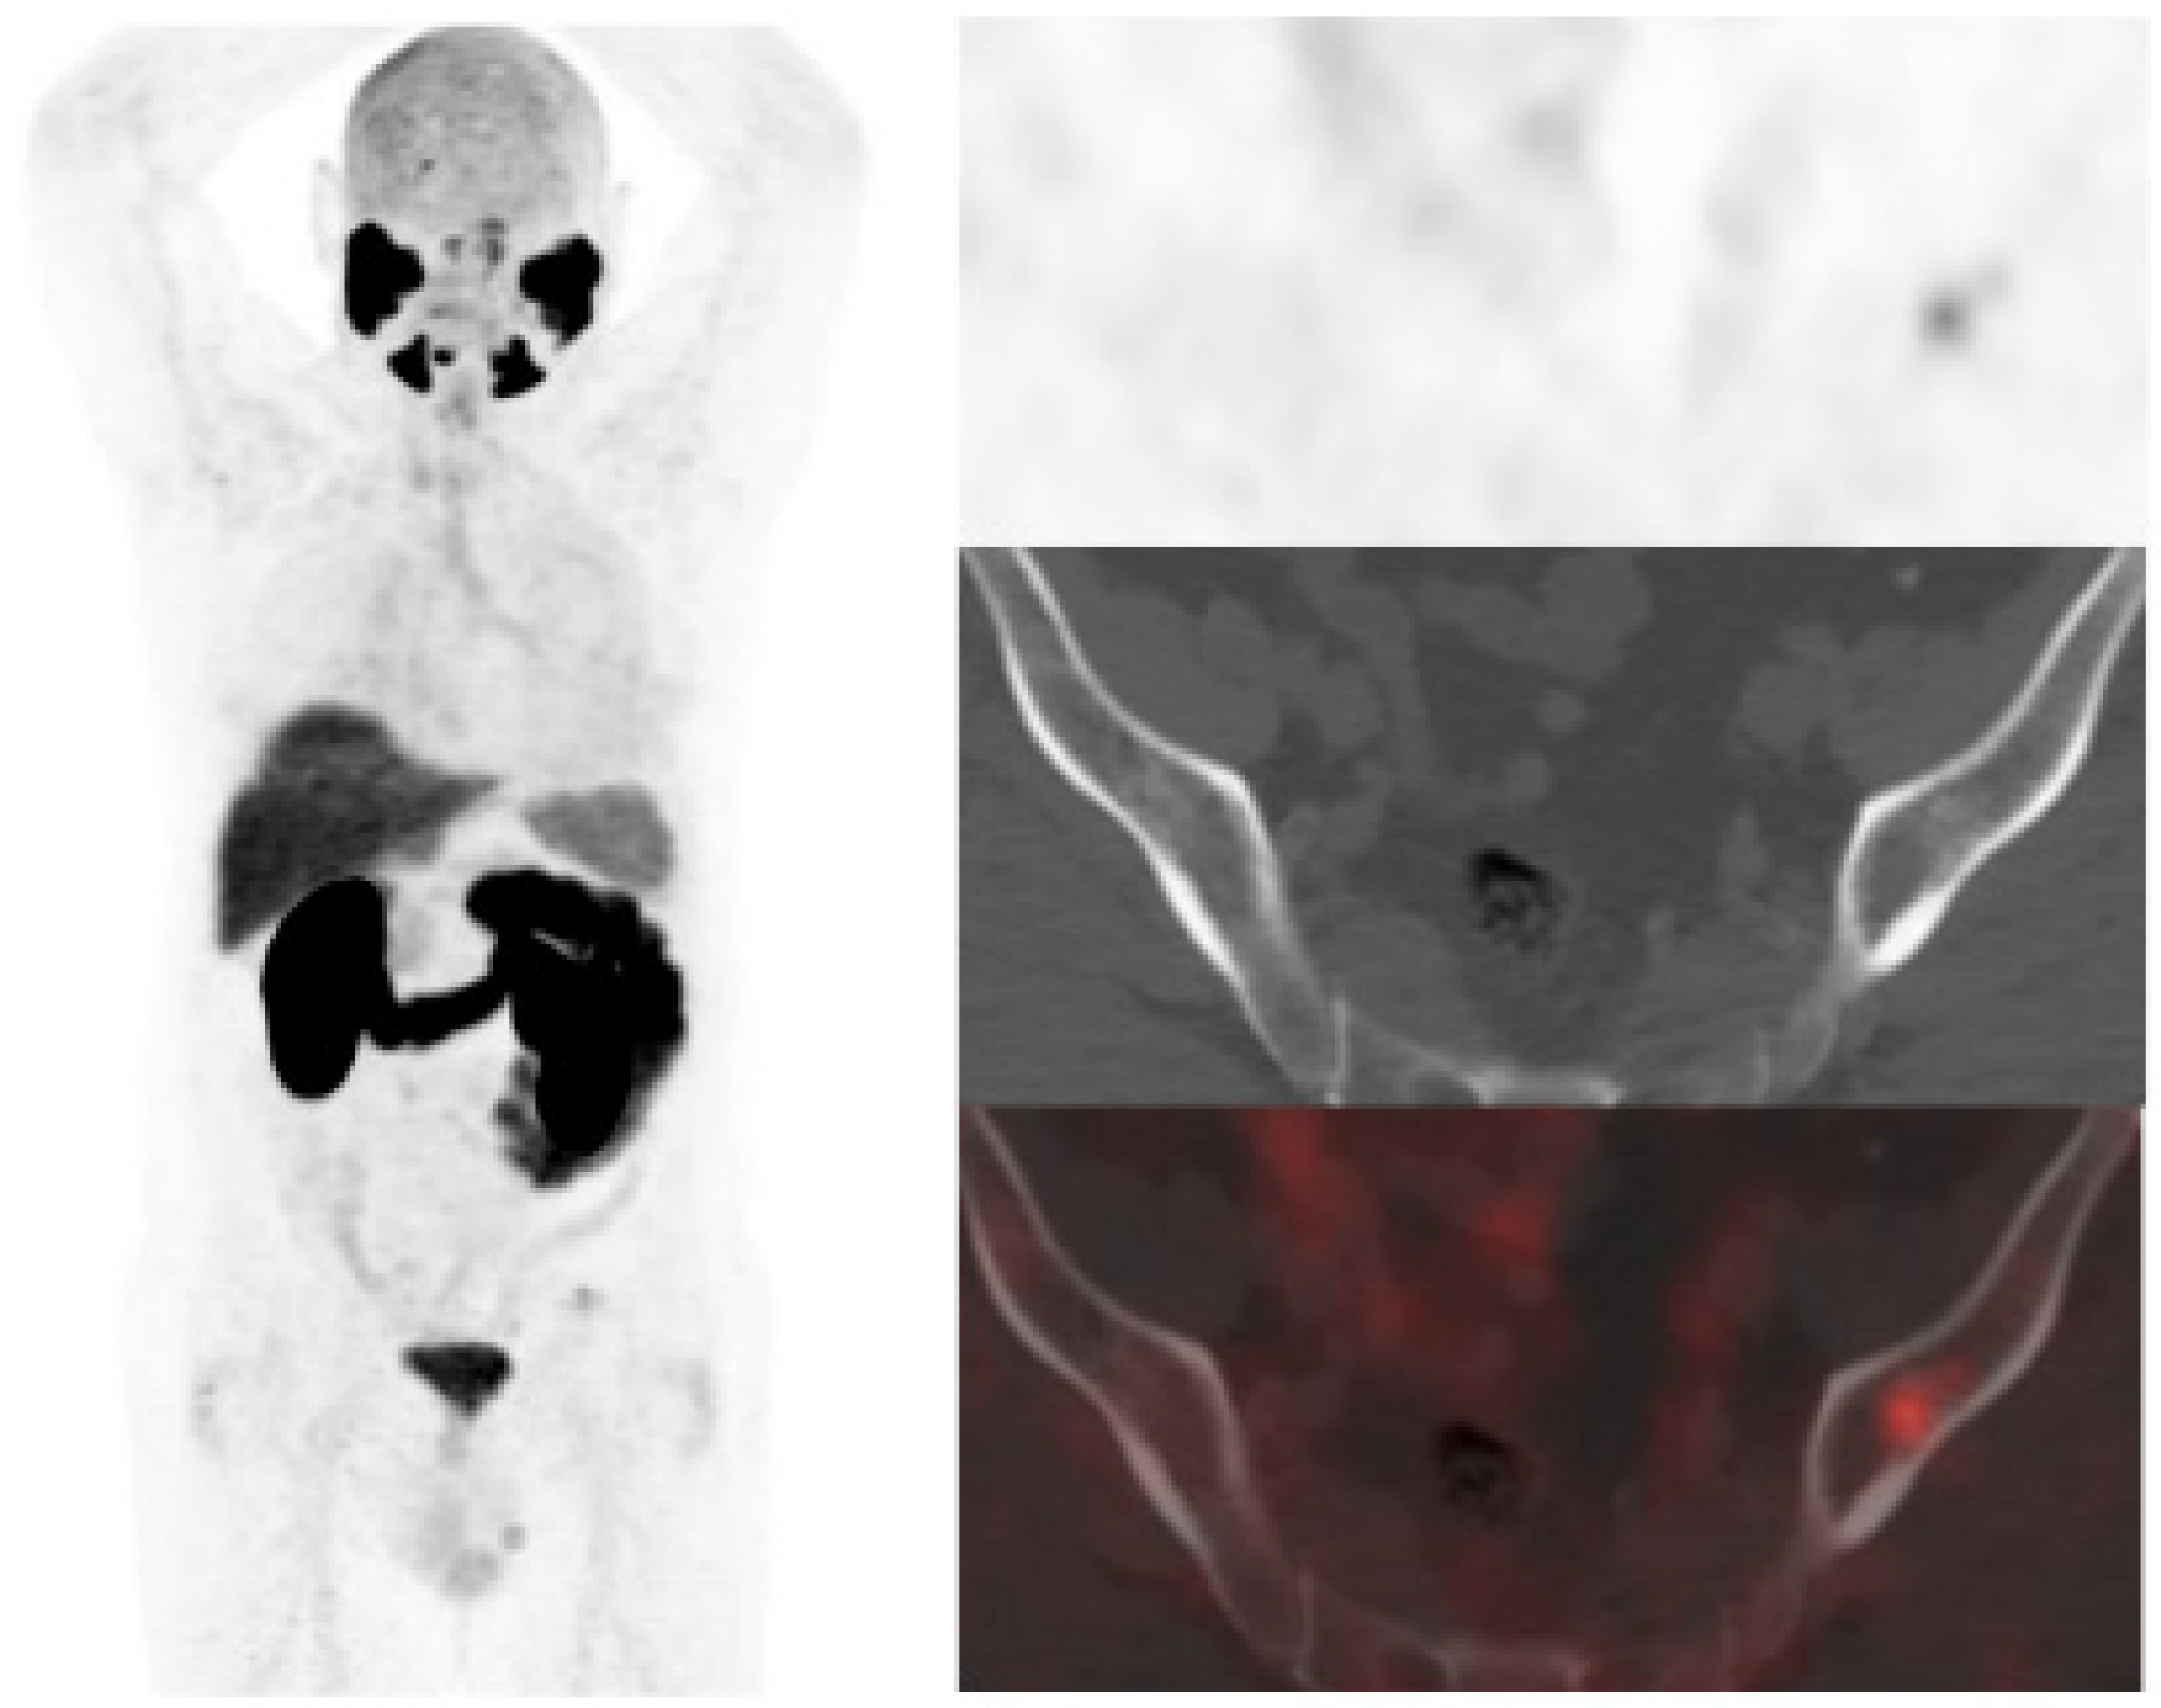

18F-DCFPyL showed a higher DR than 18F-Fluorocholine, 64.5% (89/138) and 33.3% (46/138), respectively (Table 2). Both were negative in 44 patients (31.9%) and positive in 41 (29.7%), however, in 20/41 patients, 18F-DCFPyL visualized additional lesions with respect to 18F-Fluorocholine, which entailed miTNM stage change in 17 patients (Figure 1).

Figure 1. 59-year-old patient. Gleason 7 PCa treated with radiotherapy plus ADT. After ADT withdrawal BCR was detected (PSA 2.44 ng/mL, PSAdt 2.6 mo, PSAvel 0.15 ng/mL/mo). 18F-Fluorocholine (a) demonstrated only prostatic uptake and 18F-DCFPyL-PET/CT (b) showed prostatic tracer uptake and lymph node metastasis (arrows). Time window of sixteen days between both scans. 18F-DCFPyL changed therapeutic management allowing escalation (ADT + Apalutamide).